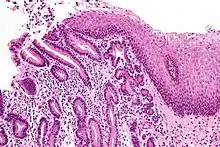

| Micrograph of a gastro-esophageal junction with pancreatic acinar metaplasia. The esophageal mucosa (stratified squamous epithelium) is seen on the right. The gastric mucosa (simple columnar epithelium) is seen on the left. The metaplastic epithelium is at the junction (center of image) and has an intensely eosinophilic (bright pink) cytoplasm. H&E stain. |